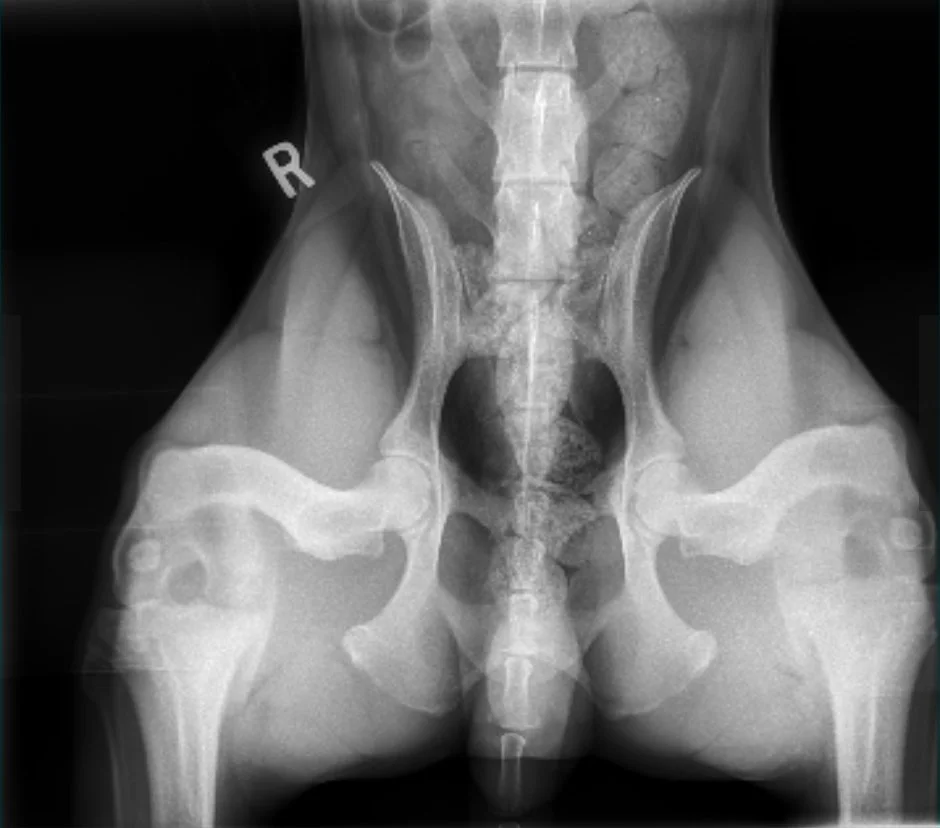

Hip X-Rays

Submitted to PennHip and OFA. Taken at 24 months of age, intact.

OFA Hips Good

PennHip: Right DI = 0.23, Left DI = 0.24. No radiographic evidence of Osteoarthritis for either hip. No cavitation present. Hawthorn’s hips rank within the tightest 5% of all dogs (all breeds) in PennHip’s database.